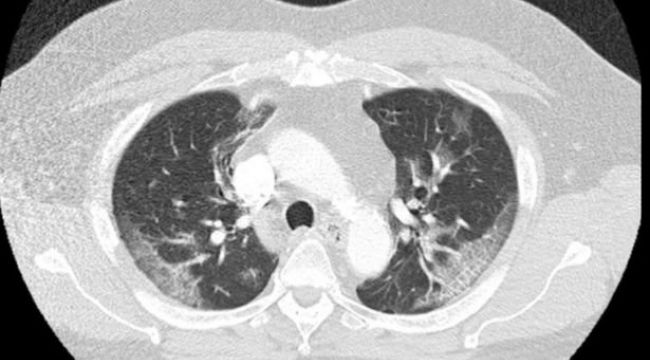

Makalede, 62 yaşındaki Chicagolu bir adamın dört gün boyunca hıçkırdığı ve bunun aralıksız devam ettiği kaydedilirken, “Hiç semptom göstermiyordu ve ateşi ölçüldüğünde de 37.3 derece ateşi vardı. Fakat hastaneye kaldırılıp testler derinleşince durum ortaya çıktı. koronavirüs testi pozitif çıktı ve ciğerlerinin kapasitesinin de düştüğü görüldü. Adamın ateşi de daha sonra 38.4’e çıktı” ifadesi kullanıldı.